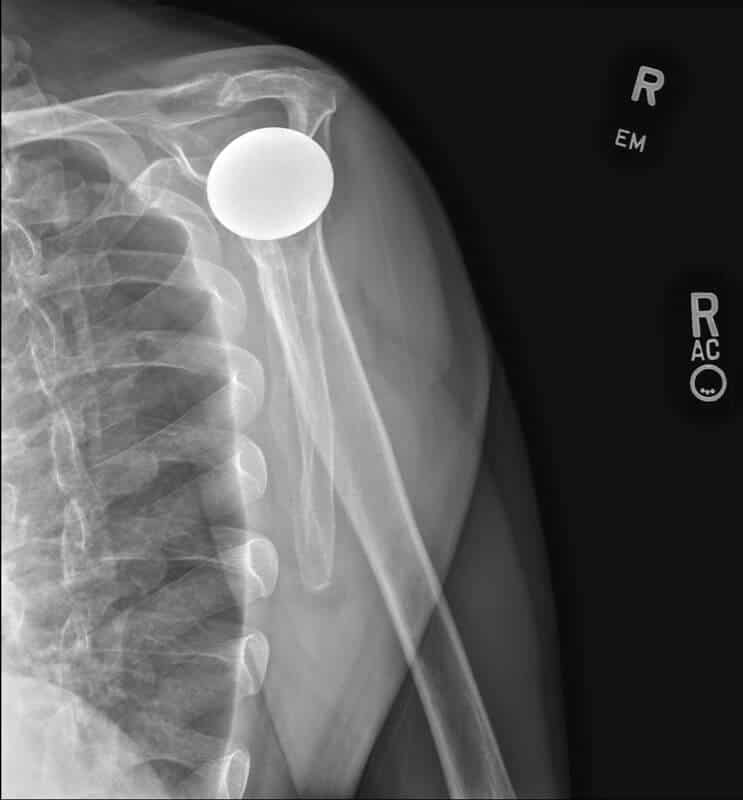

Stryker/Wright/Tornier, Simpliciti